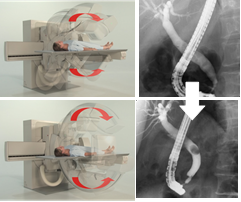

C臂旋轉(zhuǎn)多角度觀察

在內(nèi)徑與膽管、腸氣等結(jié)構(gòu)圖像重疊時,只需旋轉(zhuǎn)C臂即可將重疊的影像分開觀察,避免讓患者翻身造成內(nèi)徑脫落的風險。